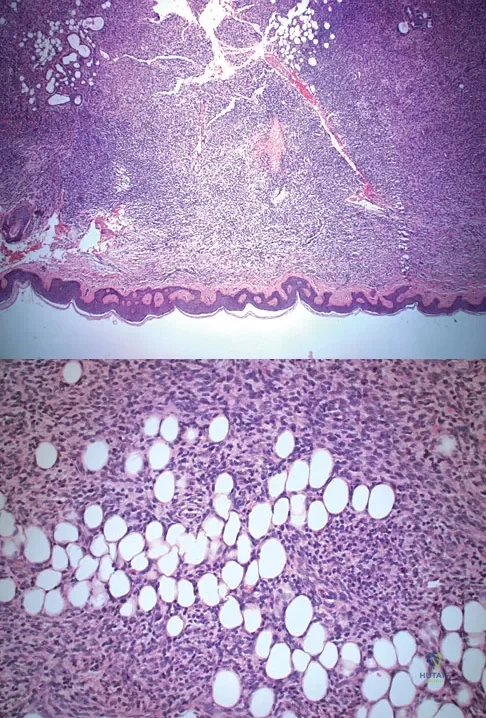

A 43-year-old woman is referred after excisional biopsy of a cutaneous soft-tissue mass from her left shoulder. Based on the biopsy specimens shown in Figures 44a and 44b, what is the best course of action?

Explanation